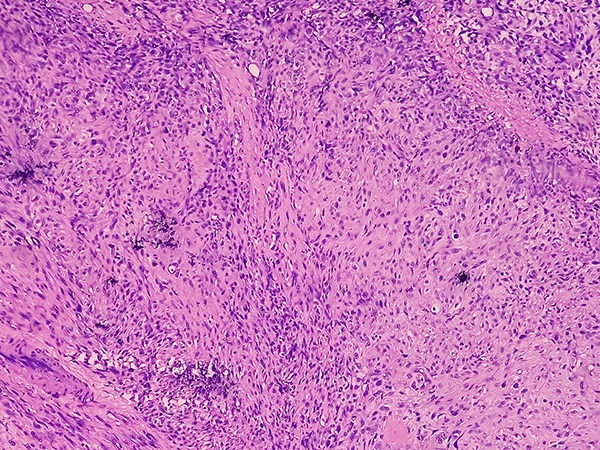

Home > Patients, Caregivers, and Advocates > About Cancer > Cancer Types > Osteosarcoma and Undifferentiated Pleomorphic Sarcoma of Bone > Osteosarcoma and Malignant Fibrous Histiocytoma of Bone Treatment (PDQ®)